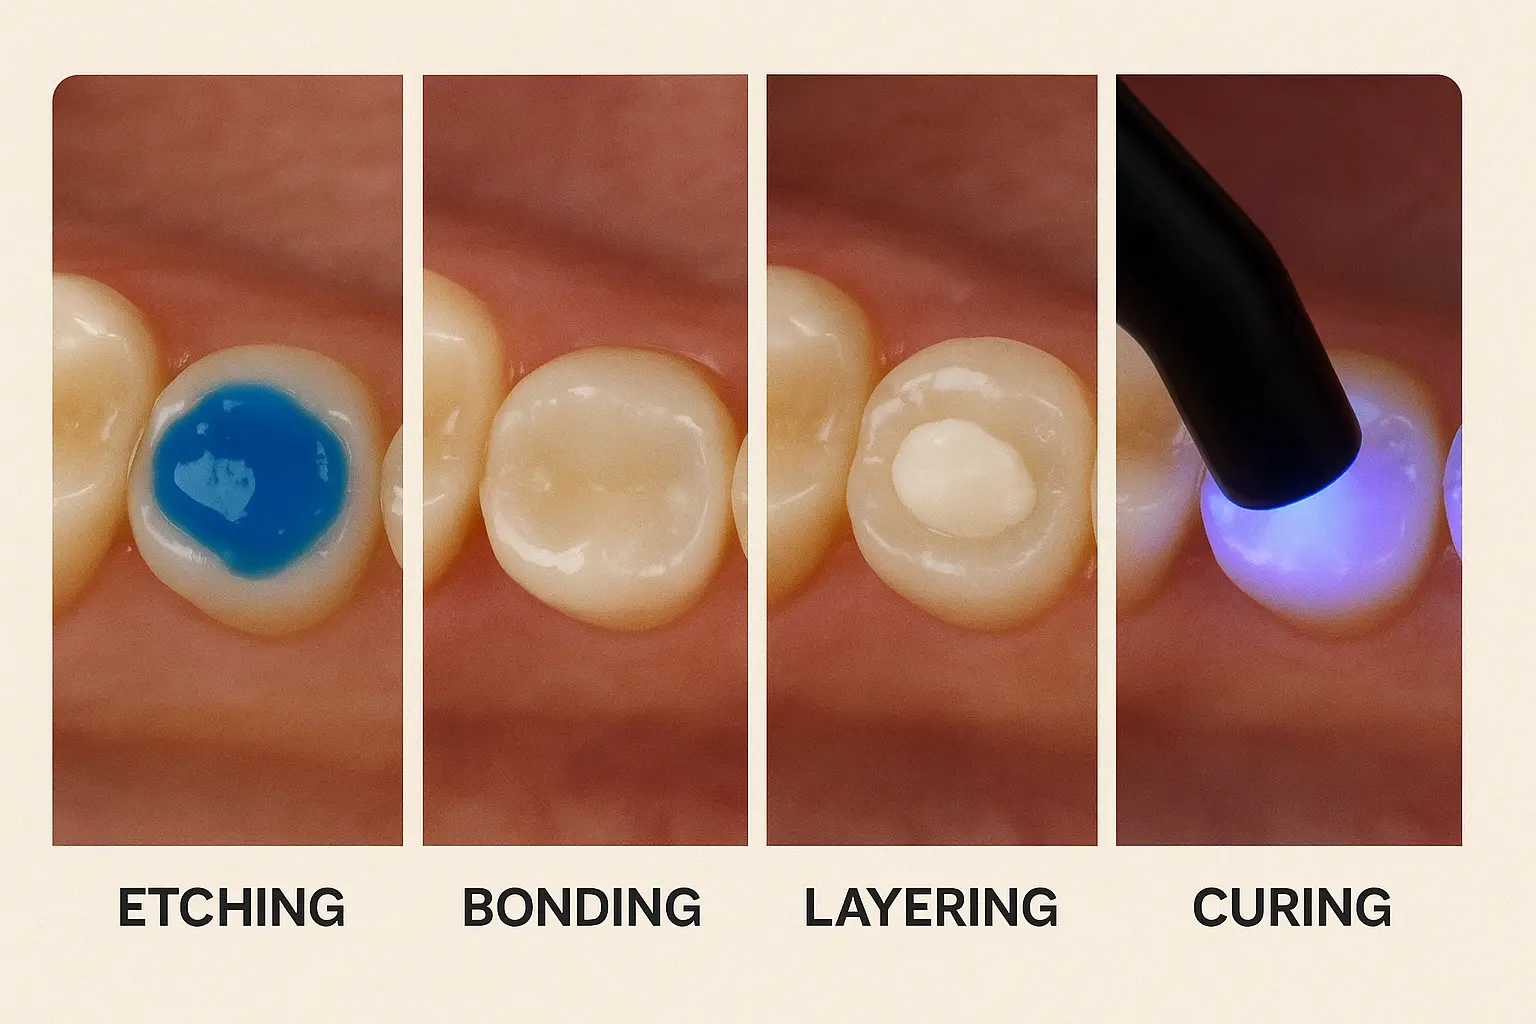

مرحله ۳: اچینگ (Etching) یا اسیداچ

سطح دندان با محلول اسیدی ضعیف (معمولاً اسید فسفریک ۳۷٪) بهمدت چند ثانیه آماده میشود. این کار باعث زبر شدن سطح مینا و افزایش چسبندگی باندینگ میشود.

مرحله ۴: استفاده از باندینگ

ماده باندینگ به سطح دندان مالیده و با نور آبی مخصوص (لامپ LED یا Halogen) پلیمریزه میشود. این مرحله پیوند قوی بین دندان و کامپوزیت را ایجاد میکند.

مرحله ۵: لایهگذاری کامپوزیت

کامپوزیت رزین در چند لایه نازک اعمال میشود. هر لایه با نور مخصوص سخت میشود. این روش لایهلایه باعث جلوگیری از انقباض و افزایش دوام ترمیم میگردد.